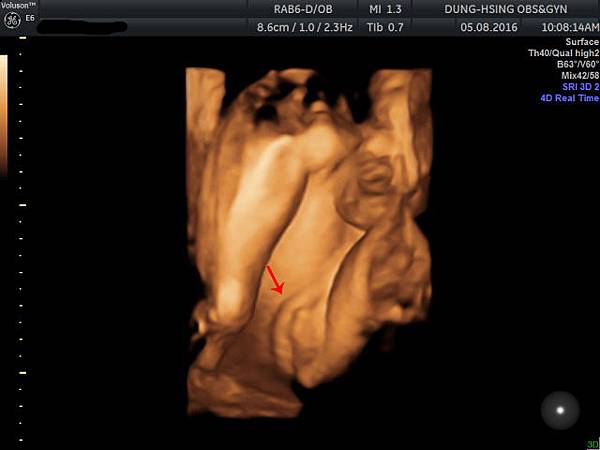

今天去照了4D超音波

主要是以嘗鮮為目的啦這機器跟高雄的產檢醫院滿類似的

順便看看寶寶到底長什麼樣子![]()

照片是她的腿骨測量右下角寫著重量1906g評估是32W.....還有點小隻表示我要繼續再吃養胎中藥

強而有力的心跳145下/分鐘不過技術人員說是148快接近男寶寶的心跳了

小妹妹的臉大鼻子厚唇跟萱萱剛出生時有點像

妹妹在笑